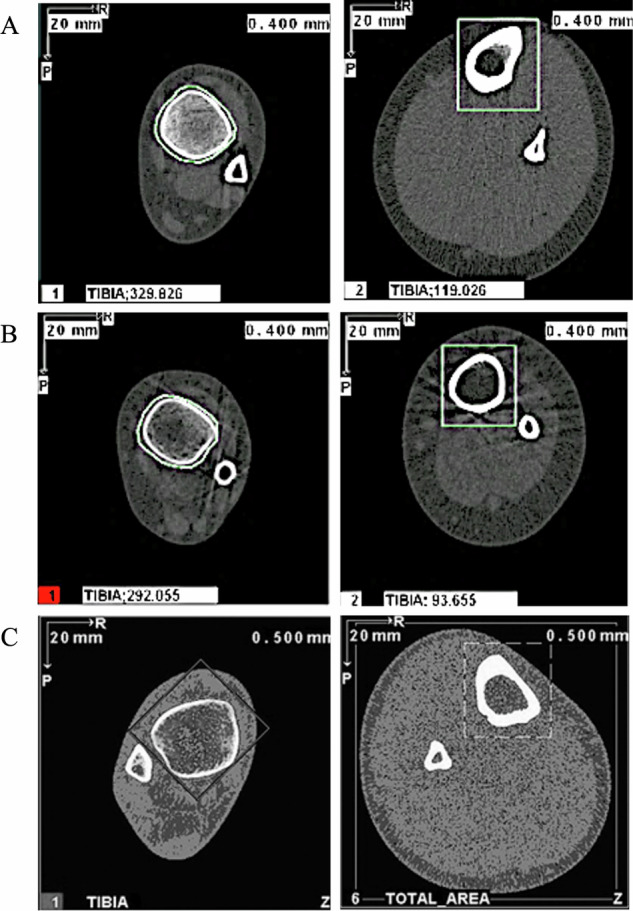

Setting: The Royal Children's Hospital, Melbourne, Australia METHODS: Ten participants with SCD were recruited and underwent peripheral quantitative computed tomography (pQCT) scans and blood tests to observe bone health biochemistry.

Results: Z-scores (mean ± SD) for trabecular density at the 4% tibial site were lower in non-weightbearing children compared to weightbearing children (-6.5 ± 1.5 vs. -2.4 ± 1.5, Total cohort: -5.0 ± 2.6). At the 66% site, muscle cross-sectional area (-4.7 ± 2.2 vs. -1.1 ± 1.7, Total cohort: -3.1 ± 2.7), strength strain index (-3.4 ± 1.3 vs. -1.0 ± 0.4, Total cohort: -2.5 ± 1.6) and total bone cross-sectional area (-2.4 ± 0.8 vs. 0.4 ± 1.7, Total cohort: -1.2 ± 1.9) were also lower in non-weightbearing children. Radial Z-scores revealed reduced total bone area at the 4% site (-3.5 ± 2.1) and strength strain index at the 65% site (-1.3 ± 1.8) in all participants. Serum testing revealed alkaline phosphatase was reduced in three participants, one of whom was also deficient in phosphate and 25-Hydroxyvitamin D.

Conclusions: Weightbearing status influenced multiple outcomes including trabecular density, muscle cross-sectional area and bone strength in the tibia.